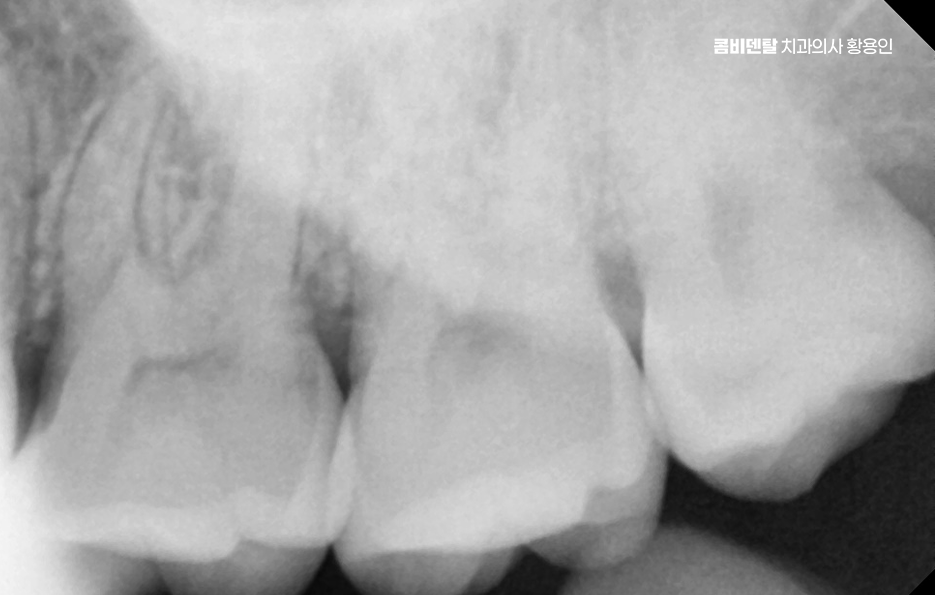

사랑니가 제대로 나지 않으면 그 앞에 있는 어금니에도 영향을 줄 수 있는데 사랑니가 비스듬히 눌러주는 방향으로 자라면 그 앞 치아 뿌리에 압박이 생기고, 치아 사이에 음식물이 자주 끼게 되면서 충치가 생기거나 잇몸 염증이 퍼지게 되는 것이며 앞 치아에 생긴 충치는 인접면 충치인 경우가 많기 때문에 일반 충치보다 더 치료가 어렵고, 경우에 따라서는 신경치료 까지 이어질 수도 있었어요.

아래 사랑니에서 문제가 생기는 대표적인 원인은 공간 부족으로 사랑니가 나올 무렵에는 앞선 치아들이 이미 자리 잡고 있기 때문에 사랑니가 나올 자리가 부족한 경우가 대부분이어서 사랑니가 잇몸 속에서 옆으로 누워서 자라거나, 부분적으로만 머리를 내밀고 자라는 일이 많다보니 이런 상태에서는 칫솔이 닿지 않아서 음식물이 끼기 쉽고, 세균이 쌓이면서 염증이 생기기 쉬운 거예요.